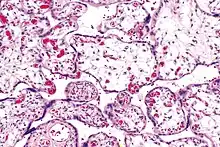

| Micrograph of villous immaturity. H&E stain. | |

Immature chorionic villi are larger and have more central blood vessels; thus, the diffusion distance for gas and nutrient exchange is larger and, therefore, placental function is impaired.

Low mag.